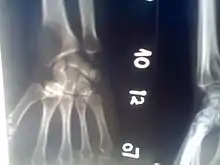

An osteolytic lesion (from the Greek words for "bone" (ὀστέον), and "to unbind" (λύειν)) is a softened section of a patient's bone formed as a symptom of specific diseases, including breast cancer and multiple myeloma. This softened area appears as a hole on X-ray scans due to decreased bone density, although many other diseases are associated with this symptom.[1] Osteolytic lesions can cause pain, increased risk of bone fracture, and spinal cord compression.[2] These lesions can be treated using biophosphonates or radiation, though new solutions are being tested in clinical trials.